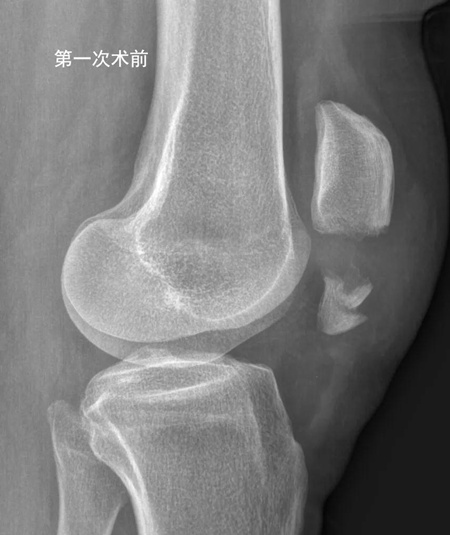

62岁洪女士,一个月前上台阶时摔倒,造成左侧髌骨下极骨折(如下图)。